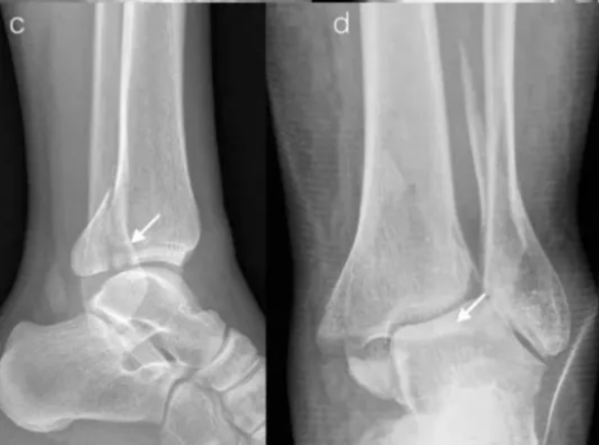

什么是Pilon骨折?

Pilon骨折是指累及胫骨远端关节面的胫骨下端骨折,常伴有腓骨骨折,多见于高处坠落、交通事故、运动损伤,严重程度取决于受伤时足部所处的位置、暴力大小、骨折粉碎程度以及软组织损伤情况。

Pilon骨折的特点是骨折累及踝关节的上负重关节面和干骺端,治疗难度大、病残率高,常导致严重的并发症如感染、畸形愈合、骨不连和创伤性关节炎。